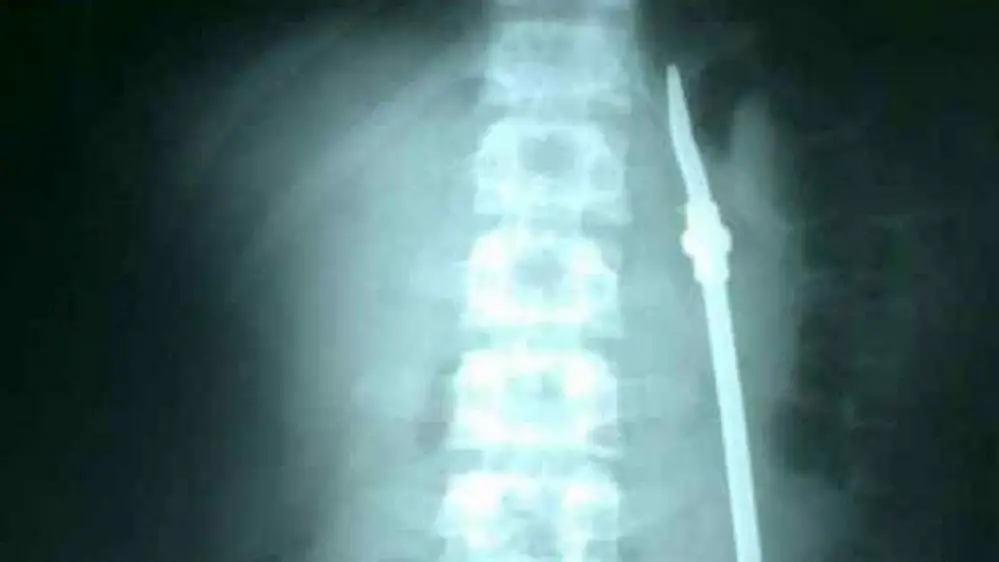

Un preso de 20 años identificado como Olivares, ingresó al hospital San Martín de Paraná, Entre Ríos, tras ingerir una bombilla, luego de tener varios problemas personales, contaron algunos allegados.

En el nosocomio, el paciente debió ser operado de urgencia. Mientras se encontraba en recuperación y con custodia, aprovechó un descuido y se escapó.